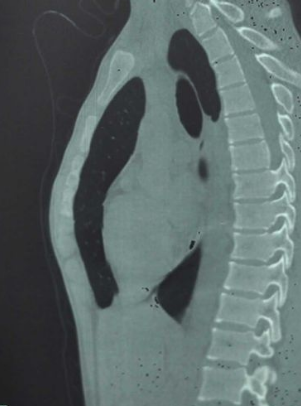

X線檢查、胸部MRI

A:先天性漏斗胸診斷依據一般可以根據胸廓的視診、胸部CT、心電圖等方面的檢查來確認,具體可以到當地的醫院做了解。先天性漏斗胸的形成可能是與遺傳、或者是伴隨有某種先天疾病導致的。患者通常表現為前胸凹陷,肩膀前伸,略帶駝背等症狀。輕微的畸形可以暫時……